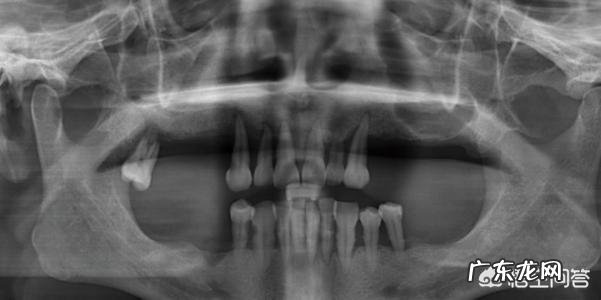

牙周炎是怎么发生的?牙周炎的发生还要“归功”于菌斑 。菌斑就是我们肉眼可见的牙齿表面的黑褐色斑块,还存在于牙结石上 。结石就像水壶中的水垢,会不断沉积,而且会朝牙根的方向堆积 。牙龈在细菌的刺激下发炎,不再紧密贴合在牙齿表面,形态也发生肿大 。于是牙龈和牙面之间出现了较大的缝隙,牙结石就会不断进入这些缝隙内,结石质硬,对柔软脆弱的牙龈形成机械刺激 。两者相互促进,不断对牙龈、牙周膜和牙槽骨产生刺激,引起炎症反应 。牙周病就是由于牙槽骨明显吸收,包裹不住牙根了,于是牙齿开始“变长”,最后松动脱落 。

牙结石压迫牙龈,龈乳头发炎,牙槽骨吸收,骨量流失太多,牙根没能完全固定,长期炎症恶化,松动变得更频繁,甚至都倾斜了,而且牙本质暴露,酸痛会越来越明显 。

怎么解决经常牙痛、牙松?1、先去拍片检查,像牙周炎的话,洗牙之后,搔刮掉牙根上的牙结石,根部变得光滑,才能阻止炎症,对于牙松,进行复合树脂牙周夹板固位,二度松动可以纤维条粘接 。